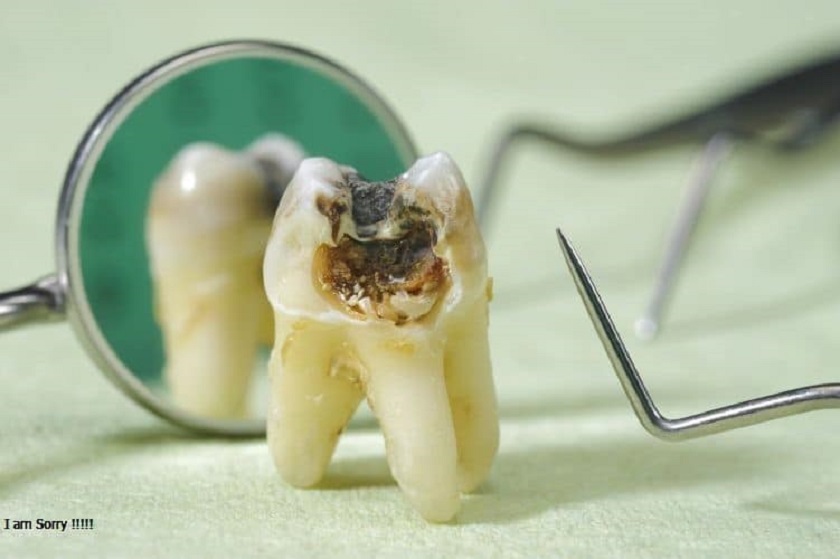

Nếu răng cấm của bạn bị sâu, sứt mẻ hay hư hỏng thì bác sĩ sẽ ưu tiên những cách khắc phục và điều trị trước. Muốn xử lý răng cấm bị sâu, hư hỏng mà không cần nhổ thì bác sĩ phải tiến hành trám hoặc bọc sứ. Ngoài ra, bác sĩ chỉ đồng ý cho khách hàng loại bỏ răng cấm ở một số trường hợp sau:

- Răng bị sứt mẻ quá lớn, gãy ngang thân răng, không thể nào khôi phục bằng phương pháp trám hoặc bọc sứ.

- Răng cấm bị sâu quá nặng, không thể chữa trị bằng phương pháp trám hoặc bọc răng sứ.